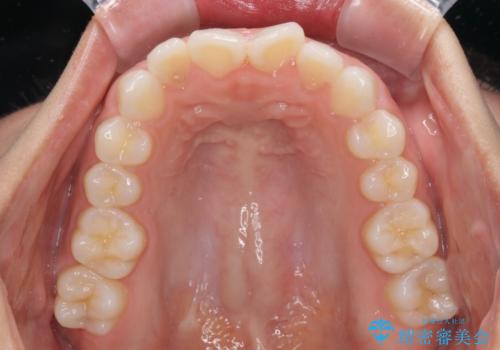

上下左右の第一小臼歯4本を抜歯して口元を下げる治療計画としました。